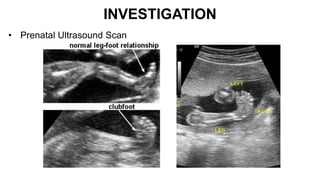

INVESTIGATION

• Prenatal Ultrasound Scan